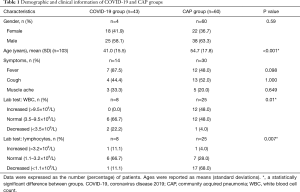

A total of 50 COVID-19 patients were initially selected for this study; however, 4 patients were excluded due to ultra-thin CT slice thickness (≤0.50 mm) with a super-resolution beyond the algorithm prediction range, and 3 patients were excluded due to poor segmentation quality as determined by the human-audited segmentation results. Ultimately, our dataset comprised 43 COVID-19 patients (mean age: 41±15 years old, of whom 58.1% were male) and 60 CAP patients (mean age: 55±18 years old, of whom 63.3% were male). The most prevalent onset symptoms, such as fever and coughing, were found in both the COVID-19 and CAP groups (Table 1). All the enrolled COVID-19 patients were classified as moderate cases according to the Diagnosis and Treatment of Novel Coronavirus Pneumonia (trial version seven) published by the National Health Commission of the People’s Republic of China (14).

Full table